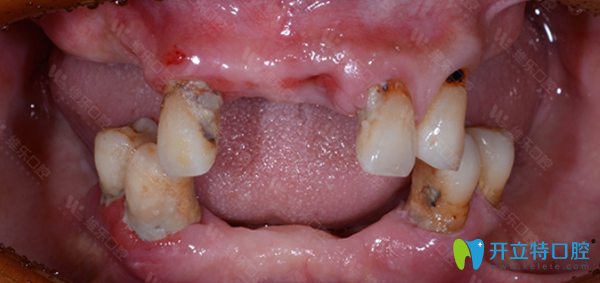

維樂口腔種牙前:

<!--<i data=20240703-sp></i>-->維樂口腔牙齒種植前

姓名:王先生 年齡:62歲

口腔問題:牙齒脫落,牙槽骨脆弱,沒有牙營養(yǎng)吸收低,整個人渾身無力。

主治醫(yī)師:翟建博 MAXI數(shù)字化疑難種植中心主任。

治療方案:全口種植。

種牙前,王大爺飽受缺牙帶來的種種折磨。經(jīng)翟建博主任仔細檢查后,建議采用數(shù)字化即刻負重種植牙技術(shù),來修復(fù)王大爺缺失的牙齒。